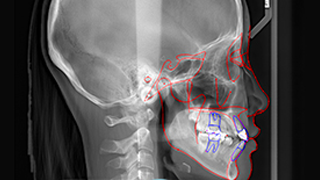

웃는얼굴치과의 12단계 교정진단시스템은 환자의 치아와 턱 구조,

얼굴 균형, 교합 상태 등을 체계적으로 분석하여

최적의 치료 계획을 수립하는 첨단 진단 프로세스입니다.

11 V-ceph

03 세팔로 촬영

환자 개개인의 치아 상태와 얼굴 균형을 정밀하게 분석하여,

맞춤형 교정 치료 계획을 수립합니다.

환자의 치아 상태와 얼굴 균형을 고려한

맞춤형 치료 계획을 수립합니다.

교정, 보철, 턱관절 등 각 분야 전문 의료진이